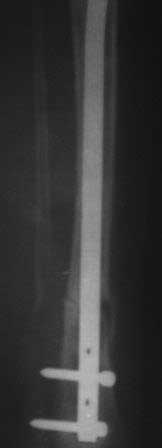

Уважаемые коллеги.Очень прощу помочь в одном сложном деле. Девочка 2005г.р. В середине 2008 г падает с велосипеда с дедом, возможно был перелом н/з костей левой голени, лечение у знахаря-табиба, но ребенок не смог бегать, часто падал, начал хромать. Май 2009г. обратились к нам, установлен д-з « вялоконсолидирующаяся перелом н/з б/берцовой кости, несросшийся перелом м/берцовой кости со смещением по ширине». Мы решили гипсовая повязка и ходьба с нагрузкой, но по категорическому требованию родителей исправить деформацию м/берцовой кости, произвели операцию ( на свою голову )»о/ репозиция и и/м фиксация спицами м/берцовой кости». Теперь началась самая интересная история! Ч-з недели две в обл. п/о раны м/берцовой открылась свищ с кровянистым выделением, гноя не было, на р-грамме лизис концов отломков м/берцовой кости, к-рый начал прогрессировать, консультирована онкологами, цитология, с подозрением направлена в центральные институты, сделана КТ, онкологическое исключили, в августе попали в остеомиелитический центр, где произведена резекция м/б на протяжение 6-7см, все зажило и выписали (снимок-1). 2010г в мае повторно получила травму, наложена гипсовая повязка (снимок-2) и через 1-2 месяца в одном из центральном институте произведена КДО аппаратом Илизарова , который снят ч-з три месяца (снимок-3) и долго ходила на костылях-мать заставила, как начала наступать, появилась деформация, заказали ортез и так ходила, но деформация прогрессировала, Обратилась к нам в апреле 2012г,(снимок-4) произведена постепенная коррекция на аппарате, и замена на БИОС 01.03.12г плечевым гвоздем, ЭОП нет, поэтому осталась несколько антекурвация (снимок-5), ребенок ч-з неделю начала ходить.Повторный осмотр 22.06.12г- деформация усиливается, за три месяца сращение очень слабое.(снимок-6). (Жаль что многие р-снимки не сохранились, мать обещала хотя бы часть найти)!Что теперь делать? Удалить дистальные винты и пробовать исправить на аппарате, или гвоздь убрать , коррекция на аппарате и после рассверливания повторный БИОС? Уважаемые коллеги, какие варианты предлагаете? С уважением Абдурашид.

Уважаемый, Абдурашид. Вы имеете дело с врожденным ложным суставом костей голени. Зная это сразу же помятуем о том, что: первое - a.Nutricia у них как такова слабо развита (а у некоторых отсутсвует покрайней мере от с/3 до н/3 диафиза), второе - разделное кровообращение эпифиза, метафиза и диафиза у детей, третье - в любом случае антекурвационная деформация во время лечения и четвертое частые рецидивы. Следовательно ошибочно принята попытка фиксация с помощью БИОС. Единственно возможное лечение на аппарате Илизарова с стимуляцией кровобращения как кости так и мягкотканного компонента обязательно. Лучше лечение проводить в специализированных центрах, где позволят койко-день и знания данной патологии. С уважением, Сергей.